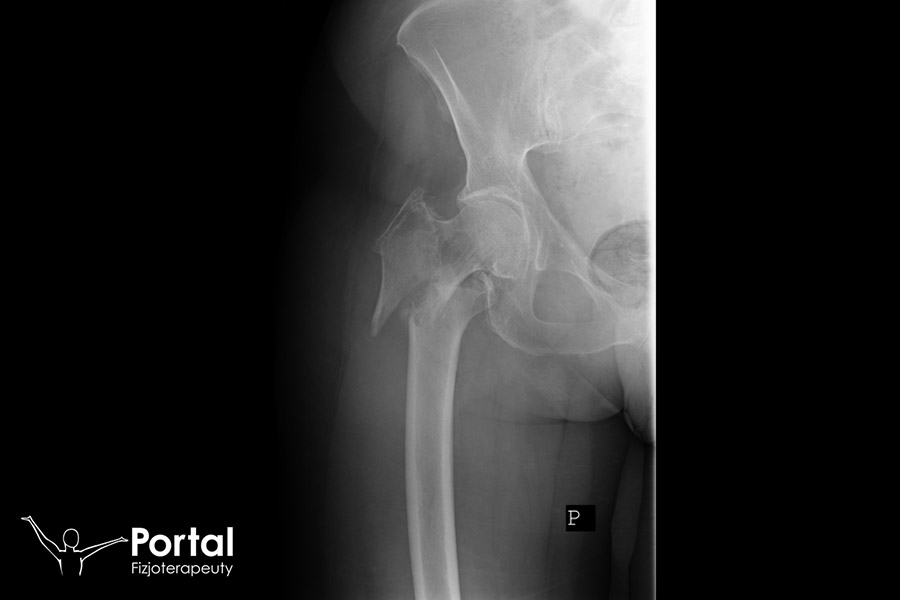

W zależności na przebieg szczeliny złamania podzielić można na:

- skośne;

- spiralne;

- poprzeczne;

- wieloodłamowe.